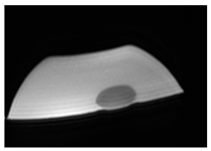

2. Materials and Methods

3. Results